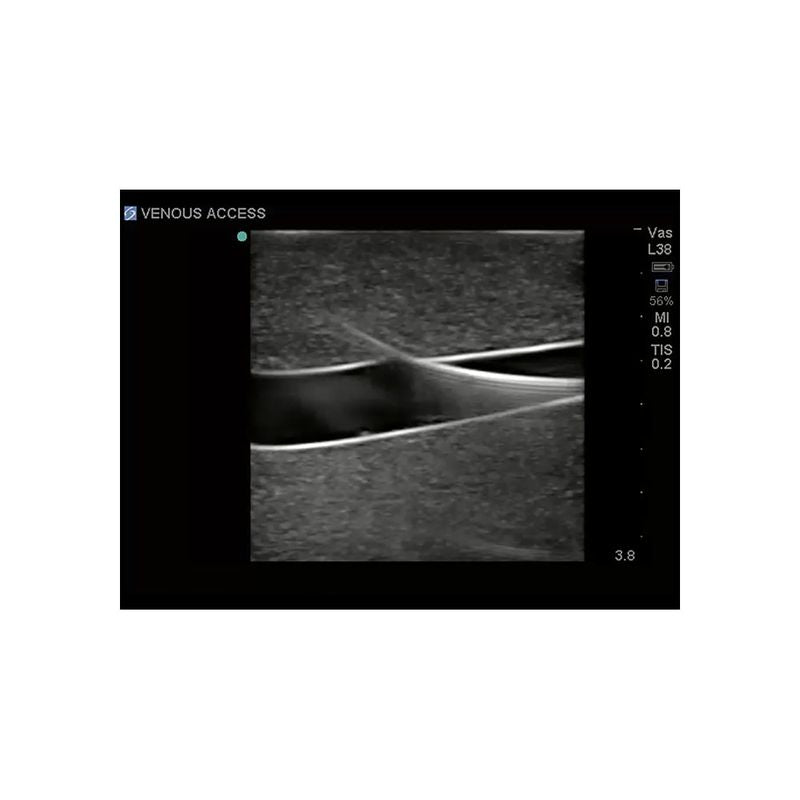

Replacement tissue insert for Central Line and Regional Anesthesia Model (BPHNB670 series).-